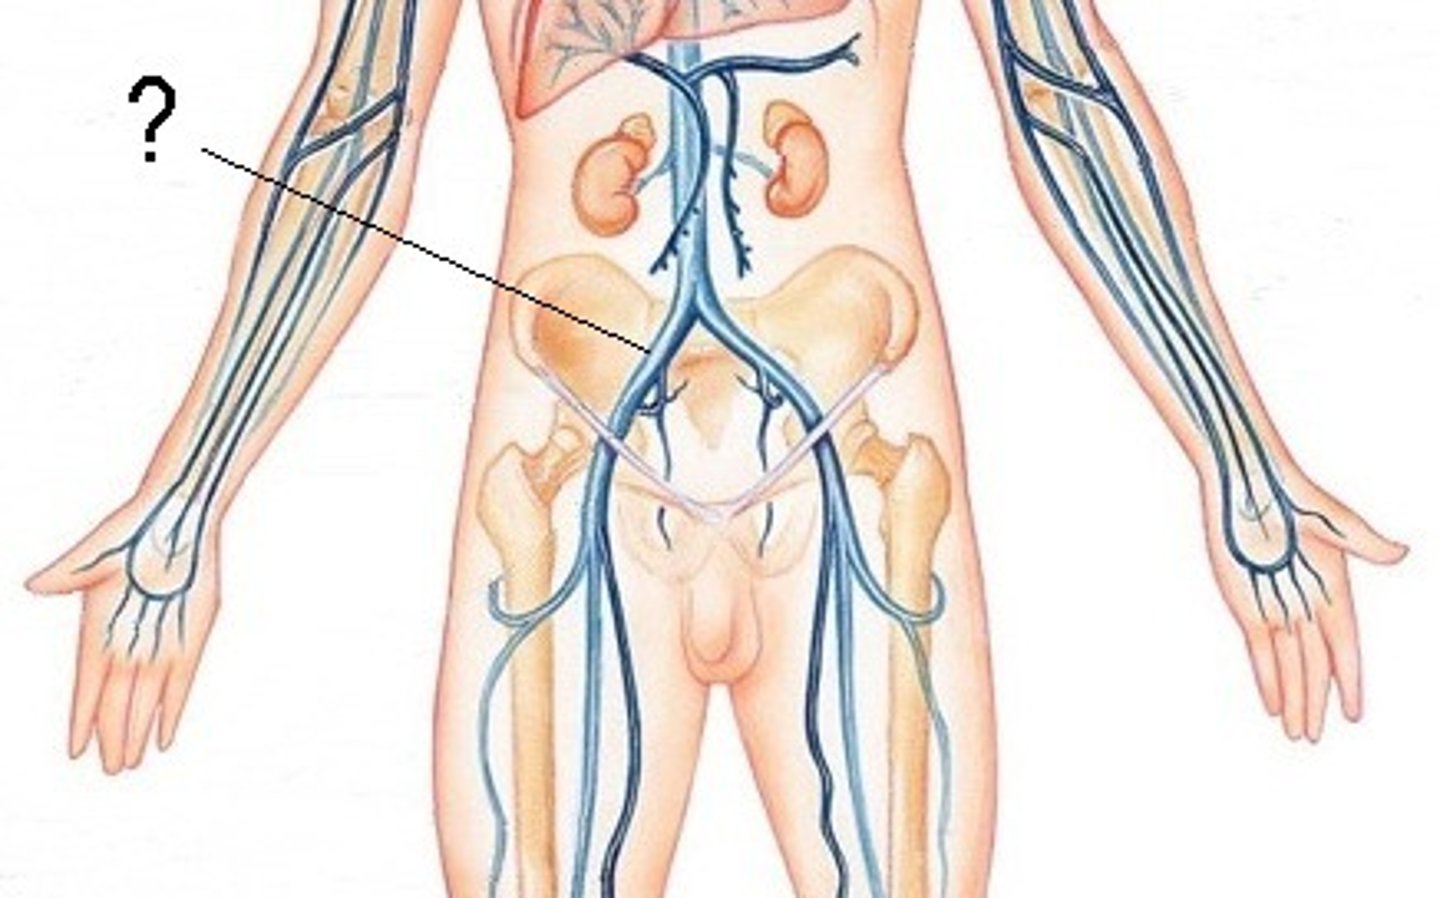

inferior vena cava

common iliac vein

femoral vein

saphenous vein